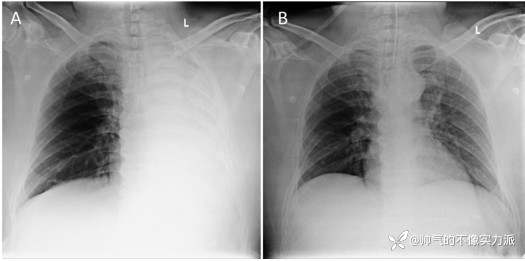

随即开始接受氧疗和雾化支气管扩张剂治疗。床边胸部X片显示左肺完全塌陷(图1A)。随着呼吸急促和氧气需求的增加,需要气管插管和有创机械通气(IMV)。

24小时后复查胸部X光片显示左肺完全扩张(图1B)。

图1

(A)胸部X线片前后视图显示左肺完全塌陷

(B)气管插管后1天拍摄的胸部X线片显示左肺完全扩张,气管插管在原位